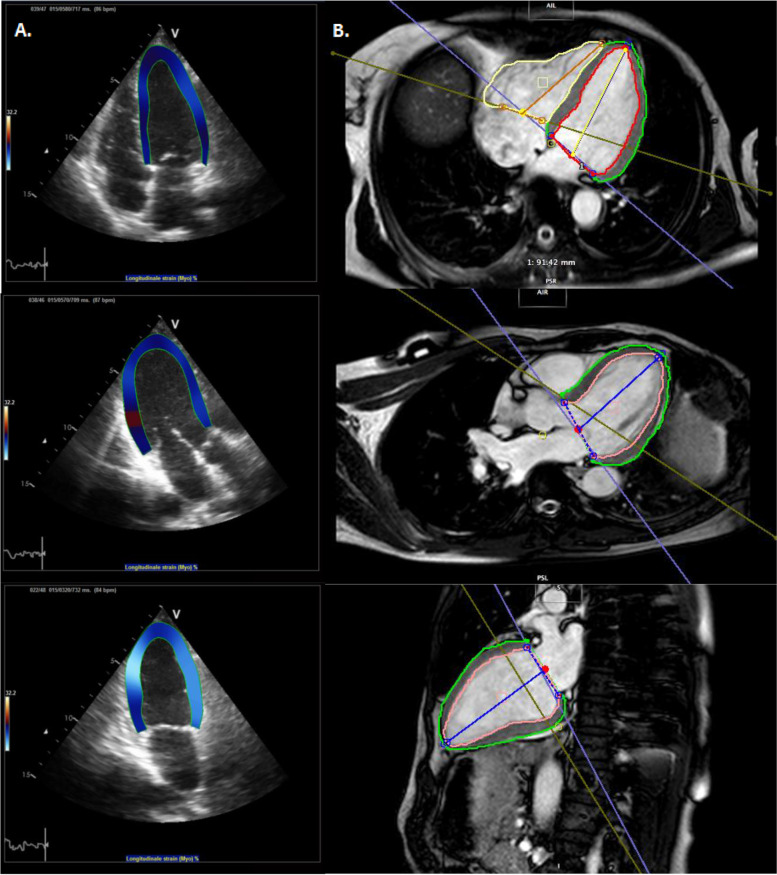

2DE was performed at the following time points: before the start of anthracycline (in early-stage patients only), before the start of trastuzumab, after 3-months (m) trastuzumab and after 6 m trastuzumab (Fig. 1, Supplementary). 2DE acquisition was performed on a Vivid 7 echocardiography system (GE Vingmed Ultrasound, Trondheim, Norway). End diastolic volume (EDV) and end systolic volume (ESV) were calculated using Simpson’s biplane method. The LVEF was determined as the difference between EDV and ESV, relative to the EDV. Baseline measurement were for early-stage patients before the start of anthracycline and for advanced-stage patients before the start of trastuzumab. Strain imaging analyses were then performed using validated tracking algorithm software (TomTec Cardiac Performance Analysis version 4.3 CPA, Unterschliessheim, Germany). EDV and ESV were automatically calculated using traced endocardial borders. These borders that were also used to calculate the GLS and GRS were manually drawn and checked by two experienced observers (Fig. 1). GLS was calculated by averaging the values of peak systolic strain of all 6 segments of the 4-, 3- and 2-chamber views. The shortening of the myocardium related to its original length is described by the negative strain values of GLS. GRS was calculated by averaging the peak systolic strain values in all 6 segments of the parasternal short-axis view at midpapillary level. The thickening of the myocardium is described by the positive strain value of GRS. Treating physicians were blinded for the strain measurements.

Fig. 1.

2D-STE and CMR images used for calculation of myocardial strain. Abbreviations: CMR cardiac magnetic resonance imaging, 2D-STE two-dimensional speckle tracking echocardiography. A. Speckle tracking analysis with 2D-STE of apical 4-chamber, 3-chamber and 2-chamber view. B. Speckle tracking analysis with CMR of transaxial 4-chamber, 3-chamber and sagittal 2-chamber view

The artificial intelligence-automated CMR software package (Circle Cardiovascular Imaging: cvi version 5.11) applying deep learning was used as post-processing software. Ventricular end-diastolic (EDV) and end-systolic volume (ESV) were measured using the short-axis stack. LVEF was calculated as the difference between EDV and ESV, relative to the EDV. Endocardial and epicardial contours of the left ventricle that were used for GLS and GRS calculation were automatically tracked using still and motion frames at end-systole and end-diastole (Fig. 1). The contours were then checked by two experienced observers, and manually adjusted when necessary. LV contours in the most basal slices were included if > 50% of ventricle wall was visible. Additionally, late gadolinium enhancement (LGE) was assessed. This technique incorporates the administration of relatively inert extracellular gadolinium contrast during gradient-echo inversion recovery imaging.